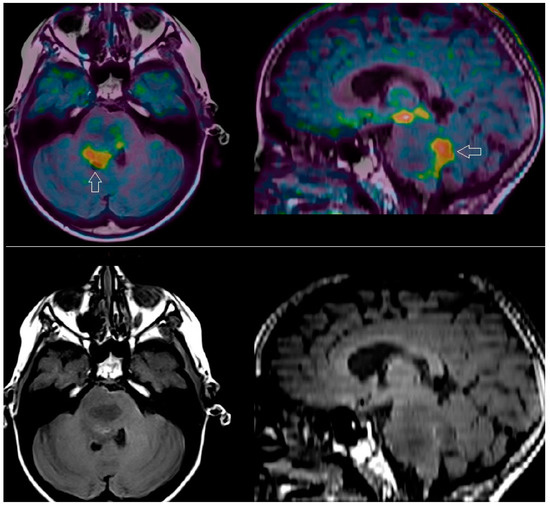

| Unterrainer et al. [23] | TSPO vs. amino-acid PET and MRI | [18F]-GE-180 | TBRmax = 4.58 BTV = 31.1 mL | [18F]-FET | TBRmax = 3.89 BTV = 19.3 mL | 0.062 0.062 | TSPO and amino-acid PET provided different parameters in HGGs according to IDH mutational status, with partially overlapping volumes, greater than those obtained with MRI. |

| Zinnhardt et al. [25] | TSPO vs. amino-acid PET and MRI | [18F]-DPA-714 | SUVmax/SUVmean = 2.5 SUVmean/SUVmean = 1.4 | [18F]-FET | SUVmax/SUVmean = 2.8 SUVmean/SUVmean = 2.1 | n.a. | TSPO and amino-acid PET provided complementary information in glioma. TSPO PET-derived parameters correlated with the amount of glioma-infiltrating immunosuppressive cells. |